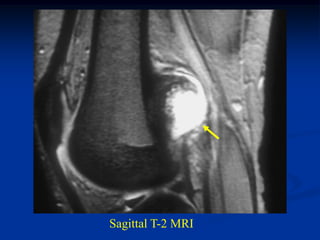

Case #589

16 year male

periosteal chondroma

distal femur

AP view